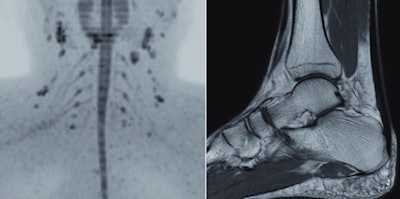

Expanding on its global R&D footprint that includes a new high-tech facility in Suzhou, China, Philips has developed a reliable and simple to use machine for developing markets. The Multiva 1.5-tesla unit is designed to ease patient discomfort and increase productivity by reducing the time spent setting up an examination. It features the FlexStream workflow system, which enables efficient handling of coils for head, spine, musculoskeletal, and neurovascular examinations, allowing a reduction of up to 40% in the time it takes to position the patient and coils before securing an image, according to the manufacturer.